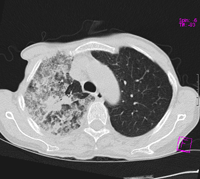

标题: CT9563:女67岁,咳嗽咯白痰伴纳差一月。右肺呼吸音低可闻及 [打印本页]

女67岁,咳嗽咯白痰伴纳差一月。右肺呼吸音低可闻及湿罗音。白细胞及淋巴细胞不高,无发烧

考虑右肺细支气管肺泡癌可能,建议进一步检查

我更趋向于2楼结核的诊断

1、右上胸廓塌陷,纵隔气管右移

2、病灶靠后方,一般结核多见一点

3、病灶内,纵隔内有少许钙化灶

3楼的肺细支气管肺泡癌也不能完全排除,毕竟患者年纪大,病史短,临床上感染症状不明显,建议短期内复查吧

病灶范围较大,病史较短,病人年龄较大,结核中毒症状不明显, 考虑1右肺细支气管肺泡癌,2.硬化性淋巴瘤,建议进一步检查